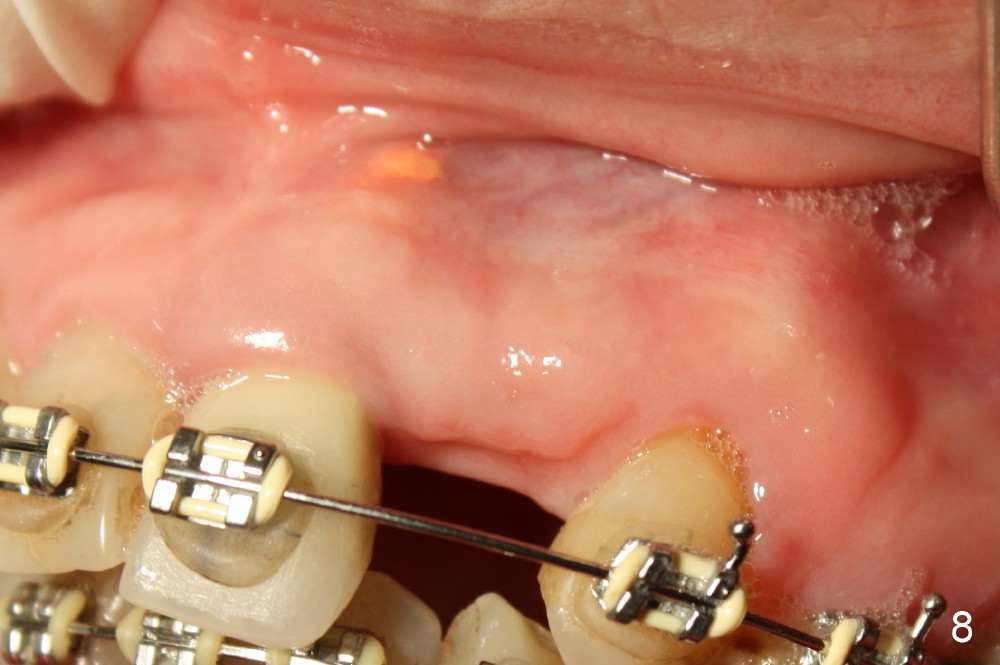

A prominent feature of implant failure in this case is pain. The patient feels that the pain is from the base of the nose. PA taken 3 days postop shows that the implant is inferior to the nasal floor (Fig.2 red ^). Clinically, the buccal gingiva continues to be erythematous 10 days postop (Fig.1). The pain is so unbearable that the implant (3.8x14 mm) is removed 10 days post placement. After repeated debridement, a 4.1 mm tap (Fig.3 T) is manually inserted with torque. A 4.1x14 mm submerged implant is placed with insertion torque < 30 Ncm, but it is placed subcrestally (Fig.4 <--). This time an immediate provisional is not provided. The flap is sutured. The pain disappears immediately. No infection is found 7 days postop (Fig.5). However, an asymptomatic vesicle is noted at the crest 3 weeks postop (Fig.6). The gingiva looks normal 2 and 3 months postop (Fig.7,8). The coronal gap dissolves 3 months postop (Fig.9 >, as compared to Fig.4), suggesting osteointegration. The implant is uncovered 4 months postop (Fig.10). Bracket is placed 5 months postop (Fig.10'). One month later, the left central incisor improves in position coronocervically (Fig.11), but the overjet needs correction by distalization of the upper anterior teeth. The implant at the site of #10 may be used as an anchorage.